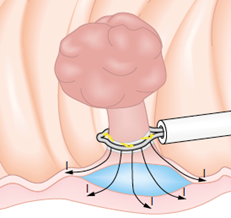

Mucosectomia é o procedimento realizado quando há necessidade de retirada de lesões maiores do trato gastrointestinal.

O exame de Mucosectomia é realizado através de injeção de liquido embaixo da lesão, através de uma agulha específica. Com isso a lesão se destaca das camadas mais profundas do intestino, diminuindo o risco de perfuração.

A retirada da lesão é feita com uma alça de polipectomia e o material é encaminhado para estudo anatomopatológico (no microscópio) da mesma forma que ocorre nas biópsias.

Mucosectomia

Para diminuir este risco, injeta-se com um uma agulha uma solução abaixo do pólipo para que ele levante e fique mais longe da parede do órgão. Após isto passa-se a alça diatérmica e realiza-se o

procedimento de polipectomia.